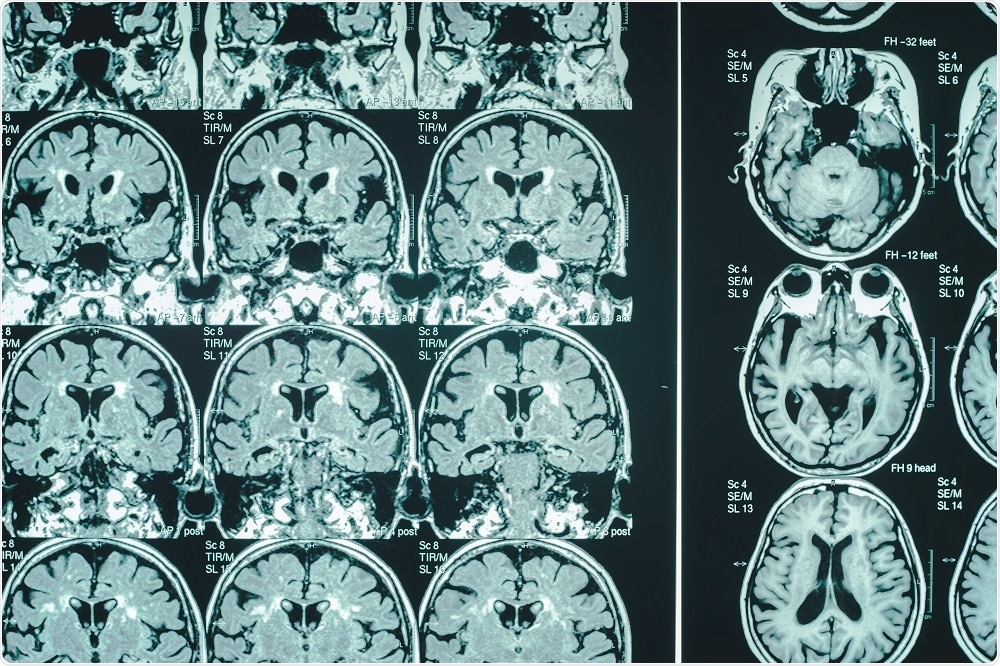

Credit: Atthapon Raksthaput/Shutterstock.com